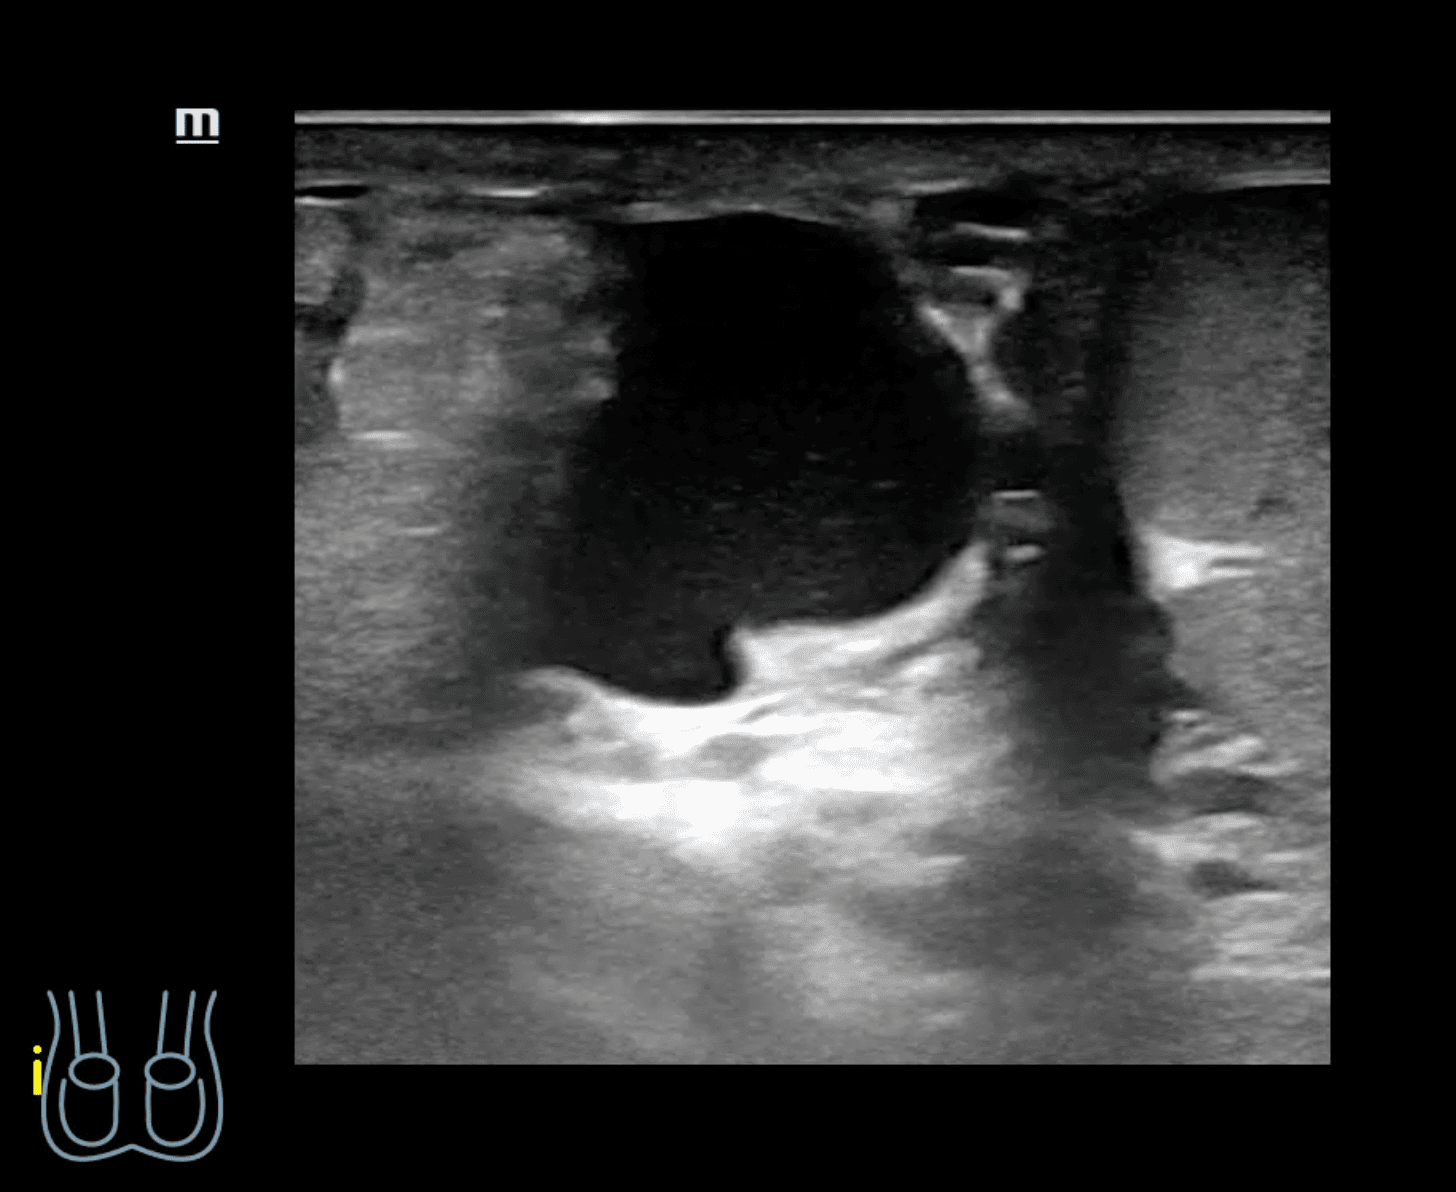

A nivel de escroto derecho, se observa imagen heterogénea con contenido intestinal compatible con hernia inguino-escrotal derecha. Testículos de aspecto normal.

Hernia inguino-escrotal derecha reductible dolorosa, no complicada.